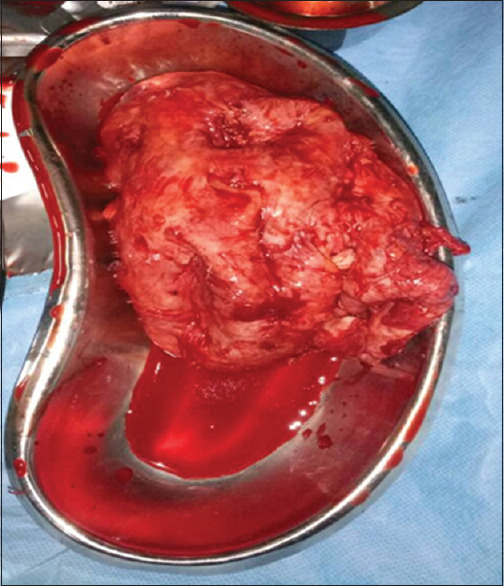

Renal ectopia, even though a benign condition, presents diagnostic challenges when its complications arise. Cold abscess in an abnormally sited kidney may, therefore, create a diagnostic conundrum for the clinician. We present the case of a 55-year-old male who had a suppurating ectopic kidney that mimicked an abdominal visceral mitotic lesion necessitating initial laparotomy, reviewed the literature, and highlighted the need to consider the differential diagnosis, especially in patients who have been referred from peripheral hospitals where generous antibiotic therapy has been instituted. We also recommend undertaking a preoperative split renal scintigraphy where available, especially when nephrectomy is considered.